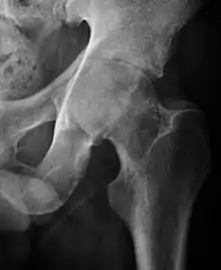

Projectional radiography ("X-ray") is the first imaging technique of choice in hip pain, not only in older people with suspected osteoarthritis but also in young people without any such suspicion. In this case plain radiography allows categorization as normal hip or dysplastic hip, or with impingement signs, pincer, cam, or a combination of both.[1]

Projectional radiography ("X-ray") is currently useful not only in older people in whom osteoarthritis of the hip is suspected but also in younger people without osteoarthritis, who are being evaluated for femoroacetabular impingement (FAI) or hip dysplasia.[1]

Plain radiography allows us to categorize the hip as normal or dysplastic or with impingement signs (pincer, cam, or a combination of both). Besides these, pathologic processes like osteoarthritis, inflammatory diseases, infection, or tumors can also be identified (Figure 1).[1]

Figure 1.

Radiography in normal hip

X-ray in pincer impingement type of hip dysplasia

X-ray of cam

Hip in osteoarthritis

Septic arthritis

X-ray in pediatrics